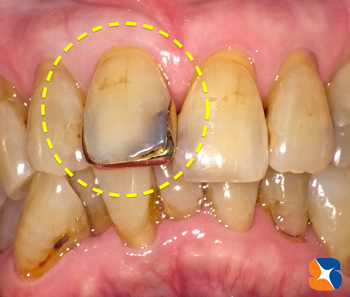

85才のお婆ちゃん、娘さんと一緒に来院。

主訴は「40年前から馴染んでいた前歯の金を取ってもらいたい。足も良くないので、治療回数を最小限でお願いします」でした。

Dr:「金の被せの歯は、中で黒く虫歯にもなっていますね。痛みは『ない』ようですので、神経を残したまま、白い被せ物を入れてみたいと思います」 続きを読む